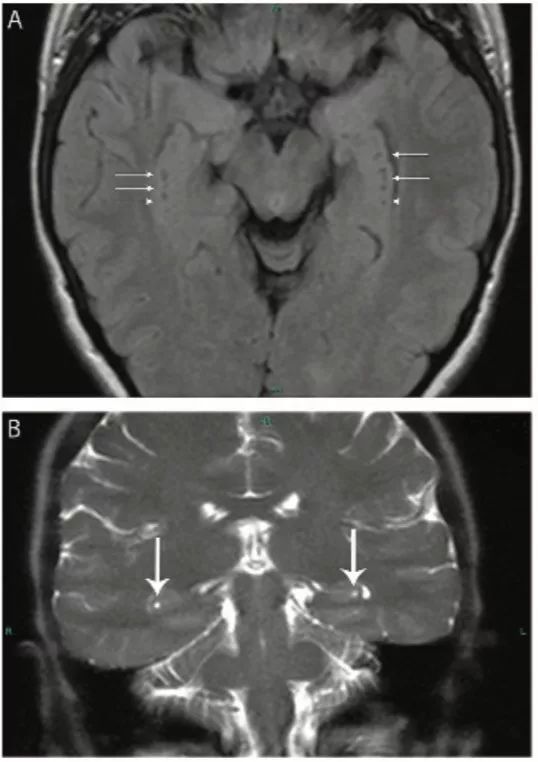

图20 脑囊虫病

轴位FLAIR(A)、增强T1IW像 (B)和冠状位增强T1WI(C)显示不同时期脑囊虫病的多发囊性病灶。囊泡期可见左额叶前部薄壁囊肿,囊内物质在FLAIR为低信号,无明显增强(楔形箭头);背外侧左额叶囊肿FLAIR高信号、增强后高信号(细箭头),为胶囊囊泡或神经囊尾蚴的颗粒状结节阶段。(C)上矢状窦相邻的两个囊肿(粗箭头)。